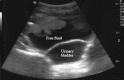

Figure 4

Suprapubic free fluid.